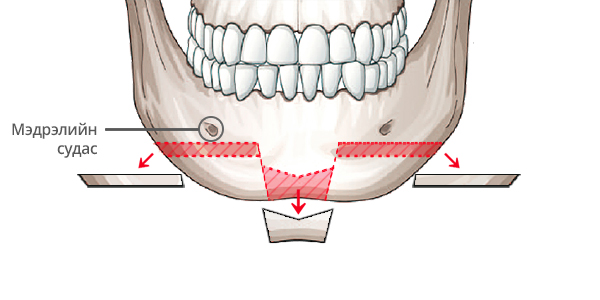

Step 2

Нүүрний уртад тааруулж ясны хэсгийг зүсэж авна.